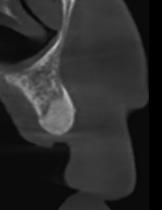

Az 50 éves nőpáciens az alsó és felső állcsont területén egyaránt panaszt (fájdalom, ráharapási érzékenység) okozó, harmadfokban mozgatható fogak miatt jelentkezett rendelőnkben. Az általános anamnézisben említést érdemlő betegség, műtét nem szerepelt. Az elvégzett klinikai és radiológiai vizsgálatok (1–2. ábra) alapján fogai reménytelen parodontális státusúnak bizonyultak, hosszú távon sem megtartásuk, sem protetikai célú felhasználásuk nem volt lehetséges. A parodontális prognózis a fogak eltávolításának abszolút indikációját jelentette. Ezáltal mindkét állcsontban teljes foghiány kialakulásával kellett számolnunk. A protetikai szemléletű, „visszafelé” tervezés elveit követtük a hosszú távú funkcionális, esztétikai siker és szöveti stabilitás elérése érdekében: mindkét állcsontban overdenture típusú fogpótlás készítése mellett döntöttünk. A megfelelő implant-protetikai rehabilitáció alapja az implantátumok megfelelő pozicionálása. A korábbi parodontális kórfolyamat következtében a processus alveolarisokat érintő eredendő csontdeficittel kellett számolnunk, amelyet tovább súlyosbíthatott volna a hagyományos extrakciós technikát követő involúciós atrófia. Ezért a páciens kivizsgálása és megfelelő előkészítése után a fog eltávolításával egy időben PRF

27 VI. ÉVFOLYAM – 2023. 4. SZÁM

Sticky Tooth segítségével kivitelezett alveolus prezerváció mellett döntöttünk, a megfelelő csontos és mukogingivális gyógyulás minőségi és mennyiségi elősegítése érdekében. A PRF készítmény mennyiségét, minőségét, kezelhetőségét és hatékonyságát jelentősen befolyásolják a páciens laborértékei, ezért kezelési protokollunk szerint a műtétet megelőzően minden esetben laborvizsgálatot végzünk (hemoglobin: 134 g/liter, hematokrit: 0,43, fehérvérsejt: 6,6 G/liter, CRP: 13,60 mg/liter, vércukor: 6,2 mmol/liter, összkoleszterin: 7,00 mmol/liter, triglicerid: 1,08 mmol/liter, HDL koleszterin 2,57 mmol/liter, LDL koleszterin 1,12 mmol/liter), D3 vitamin: 117,5 nmol/liter).

A fogak eltávolítása és az alveoláris csont megőrzésének és regenerációjának segítése céljából elvégzett augmentáció altatásban történt. Óvatos, atraumatikus extrakciót követően eltávolítottuk a parodontális és periapikális gyulladásos folyamatok eredményeként jelen lévő sarjszövetet. A bukkális csontfal hiánya és a tervezett vertikális augmentáció miatt indokolt membrántechnika megfelelő kivitelezése céljából a felső állcsonton mukoperioszteális lebenyt képeztünk (3–4. ábra). Az alveolus prezervációt Sticky Tooth, PRF és titánerősítésű teflon (PTFE-Ti) membránok segítségével végeztük el, a J. Choukroun által megadott vérvételi és centrifugálási protokoll (28) elveinek betartásával: kizárólag Process for PRF Duo Quattro System eszközöket, centrifugát, vérvételi egységet és csöveket, a membránok előállításához PRF Boxot használtunk. Az A-PRF és S-PRF csöveket a PomPac eljárásnak megfelelően 4 Celsius-fokra előhűtöttük. Az eltávolított fogak makroszkópos tisztítását és darabolását nagy fordulattal (300 000 RPM) fogászati turbinába helyezett gyémántfúróval végeztük, majd Tooth Transformer™ berendezéssel, annak gyári reagens rendszerével kezelt őrleményt nyertünk. A Sticky Tooth készítmény előállítása a PRF készítmény és az őrlemény